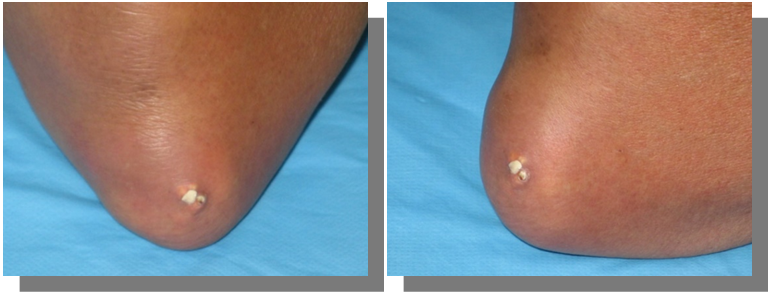

Chronic gout

If the condition is left untreated, hyperuricemia persists, most patients develop more frequent acute attacks, less intense usually but may affect multiple joints at the same time or in rapid succession. Over time there will be subsequent deposition of MSU crystals in the joints, tendon sheaths, over bony prominences, and in subcutaneous tissues called tophi. Tophi are recognized as hard swellings whitish to yellow coloured under the skin, some may break and discharge chalky material containing MSU crystals. they have a predilection to common sites; the ear pinnae, olecranon or prepatellar bursae, the distal interphalangeal joints, the dorsum of the MTPJ, and metacarpophalangeal joint (MCPJ) (Figures 7–9).